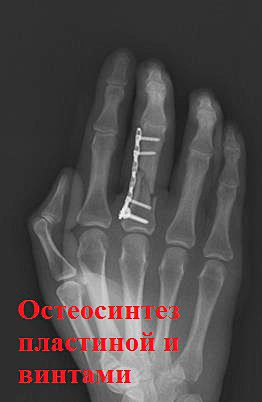

В связи с неудовлетворительным положением отломков после репозиции было принято решение выполнить операцию.

Положение на отломков на контроле удовлетворительное.

Еще один клинический случай…

После операции